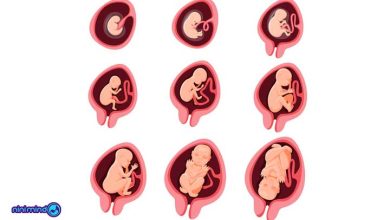

مراحل تشکیل جنین | لقاح و شکل گیری جنین

آیا با مراحل لقاح و تشکیل جنین آشنایی دارید؟ پس از تشکیل سلول تخم، تقسیمات سلولی صورت گرفته که رشد…